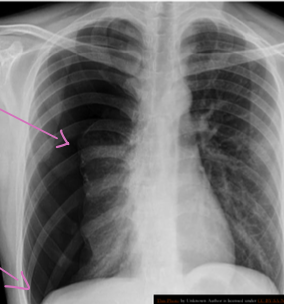

Patient with severe chest truama, Respiratory rate only 8/minute due to restricted chest movement

Case 2 Z

A 32 years old male presented with history of low grade fever, cough with sputum, sometimes blood stained. He has weight loss of 5 kg during this period. His chest X-Ray is shown ABOVE.

A 32 years old male presented with history of low grade fever, cough with sputum, sometimes blood stained. He has weight loss of 5 kg during this period. His chest X-Ray is shown ABOVE.

Describe the abnormality seen in the X-Ray?

- Cavitation and consolidation in the left upper lung

- bilateral Hilary lymphadenopathy

What is the likely diagnosis? Pulmonary TB

Mention 2 other investigations which you will advise?

- o Sputum culture and smear

- o IGRA

Mention 2 factors which increase the risk of this disease?

- HIV

- Chemotherapy

Mention 2 drugs used to treat this medical condition?

- o Rifampicin

- o INH (Isoniazid)